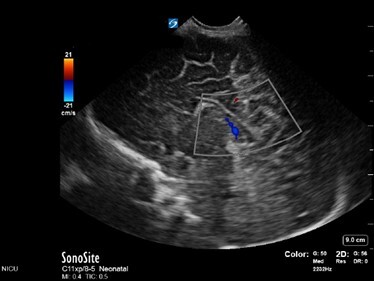

Neonatology Normal Anatomy Medium Velocity Low Flow Image